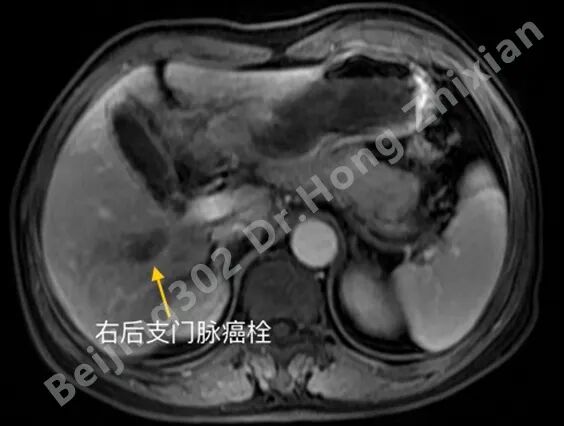

临床随笔丨肝癌术前新辅助治疗:“更优选择”还是“过度治疗”?

病例简介